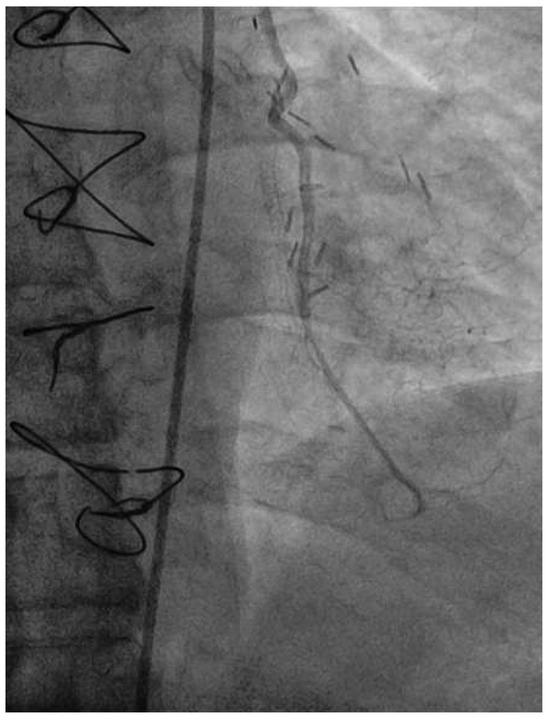

Following RA, both LAD and diagonal were wired with ease using separate Runthrough (Terumo, Japan) wires. Predilatation of both bifurcation limbs was undertaken using 1.5 × 15 mm Trek (Abbott) and 2.0 × 10 mm Sapphire (Orbus-Neich, Hong Kong, China) semicompliant balloons, which both expanded well at nominal pressure. Intending to perform an elective T-stent strategy, a 2.25 × 28 mm Promus Premier DES was deployed at 18 Atm in the diagonal branch, landing proximally at the ostium of this vessel (Figure 3). After removal of the diagonal wire, a 3 × 38 Promus Premier stent (Boston Scientific) was sited from the origin of the LMS across the first diagonal and deployed at 18 Atm (Figure 4). The diagonal branch was then rewired with the runthrough wire. A kissing inflation was performed at 12 Atm using a 3.5 × 12 Quantum (Boston Scientific) and 2.5 × 12 Sapphire noncompliant (NC) balloons in LAD and diagonal, respectively (Figure 5A). The proximal LAD and LMS were then optimised using the 3.5 Quantum NC (LAD) and a Hiryu (Terumo) 4 × 10 NC (LMS) balloons at 22 and 18 Atm, respectively (Figure 5B). The final angiographic result was excellent (Figure 6). Intravascular ultrasound of the LMS was not undertaken as angiographically the LMS stent already appeared completely expanded and oversized. We opted not to intervene in the ostial left Cx in order to best preserve the geometry of the LMS stent.

Figure 4. LAO 30°, cranial 30° view. A Promus Premier 3.0 × 38 stent has been deployed from ostium of LMS across the diagonal.